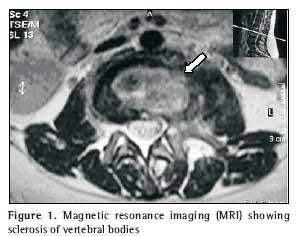

As her condition worsened, leading to difficulty in moving about, she was advised to seek medical assistance at a neurosurgery outpatient clinic, where she was submitted to lumbosacral spine computed tomography, magnetic resonance imaging, chest X-ray, biopsy of the affected site and blood count (including determination of erythrocyte sedimentation rate). Computed tomography revealed irregularity and reduction of the articular space between L2 and L3, concomitant with sclerosis of the corresponding vertebral bodies, as well as fracture in L2. The vertebral disk between L5 and S1 presented a slight protrusion, without causing significant intrarachidian repercussions. The findings suggested the possibility of an inflammatory or infectious process, or both, involving the L2 and L3 vertebral bodies, as well as the corresponding intersomatic disk (Figure 1). Magnetic resonance revealed reduction of the L2/L3 disk space and cold abscess in the corresponding area, which reinforced the possibility of a spondylodiscitis-like process (Figures 2 and 3).

Magnetic resonance is the most sensitive and most specific method for differentiating the nature of the vertebral collapses, in addition to showing early alterations(9,18,19) that aid in diagnosing tuberculous spondylitis(20). However, it may produce similar imaging results in cases of vertebral neoplasia and infection by pyogenic bacteria(9, 21).

In pyogenic infections, reduction of the intervertebral space is atypical(20,22). Nevertheless, for our patient, the imaging revealed intervertebral reduction concomitant with involvement of consecutive vertebrae, both of which are considered characteristic of tuberculous spondylitis(9).